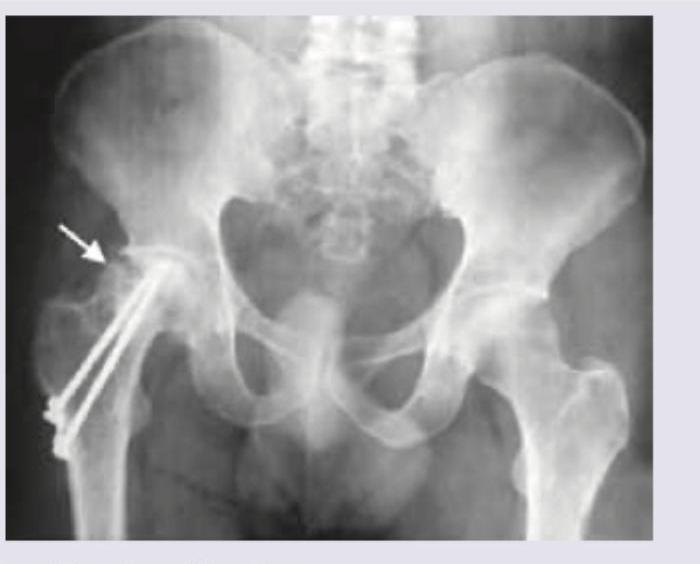

Which of the following classifications is used to assess the fracture shown below?

Explanation: ***Pipkins classification*** - The image shows a **femoral head fracture**, indicated by the arrow, with internal fixation. The Pipkins classification system specifically categorizes fractures of the **femoral head**. - This system helps guide treatment and prognostication for these particular hip injuries, differentiating based on location and associated injuries. *Gustilo classification* - The Gustilo classification is used for **open fractures**, assessing the extent of soft tissue damage and contamination. - The image displays a post-operative X-ray of a surgically fixed fracture, and the classification is not applicable here as it pertains to the initial presentation of an open fracture. *Salter and Harris classification* - The Salter-Harris classification system is used for **growth plate (physeal) fractures** in children. - The image shows a fracture in an adult bone (as evidenced by the fused growth plates and the morphology of the bone), making this classification irrelevant. *Weber classification* - The Weber classification is used for **ankle fractures**, specifically those involving the distal fibula. - The fracture shown in the image is of the **femoral head**, not the ankle, hence the Weber classification is not appropriate.